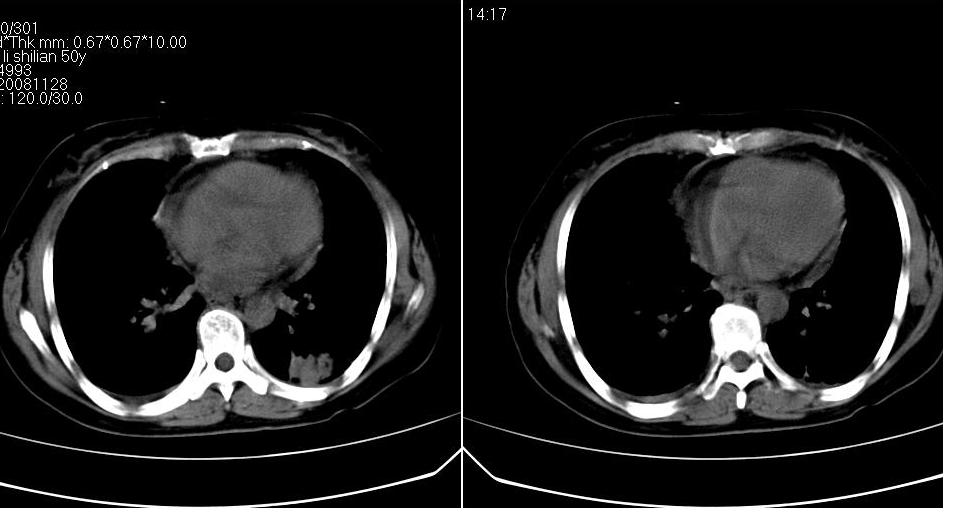

标题: CT16839:胸部CT平扫

女 50岁,在其他医院确诊肺癌.

考虑 肺癌伴肺及纵隔转移,心包膜增厚